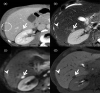

MRI is widely used in clinical practice for detecting liver diseases. Since the introduction of gadoxetic acid, MRI has become the most effective modality for the detection and characterization of focal liver lesions. According to previous meta-analyses, the area under the receiver operating characteristic curve (AUROC) was 0.97-0.99 for the diagnosis of small hepatocellular carcinoma (≥ 2 cm) by gadoxetic-acid-enhanced MRI. Moreover, the AUROC for the diagnosis of colorectal liver metastases was significantly high (0.98). Despite gadoxetic acid's drawbacks, its clinical utility outweighs them, making it the contrast agent of choice in routine liver MRIs. Moreover, clinically, liver MRI has become more prevalent for a quantitative assessment. Liver fibrosis can be evaluated using MR elastography; whereas, hepatic steatosis and iron overload can be evaluated using proton density fat fraction, with high accuracy and reproducibility. This article reviewed the usefulness of liver MRI, which can be a comprehensive imaging modality in clinical practice.